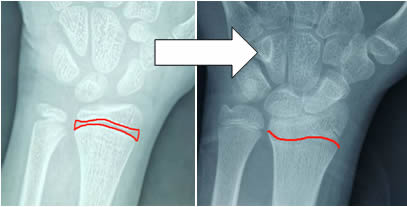

未成熟的長骨在結構上包括骨骺和骨幹兩(liǎng)個部分。骨骺與幹(gàn)骺端之間的軟骨,呈現在骨齡(líng)片中是(shì)透光帶,91成人网站稱之為(wéi)骺板或(huò)生(shēng)長板,其本質是(shì)軟骨,正是軟骨的(de)存在,骨才(cái)能不斷生長變長,人才能長高(gāo)。隨著青春期來臨(lín),性激(jī)素分泌增加,生長板逐漸鈣化(huà),被骨組織取代,剩下一條緊密的縫,骨齡片中透(tòu)光帶模糊以至消失,也就是家長(zhǎng)們逐漸熟知的“骨骺線閉合”,這標誌著(zhe)長骨停止生(shēng)長,人的身高增(zēng)長趨於終止,如下圖。